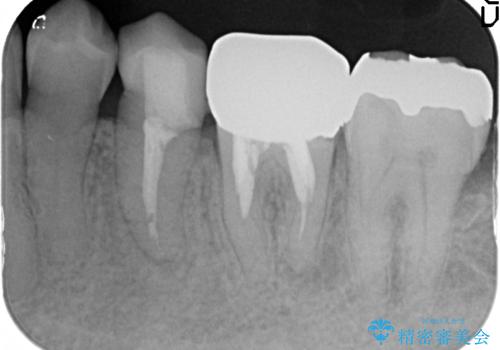

- 左下6番目の銀歯をオールセラミッククラウンにやり替えた症例です。

根管充填が不十分だったため再根管治療も行っております。